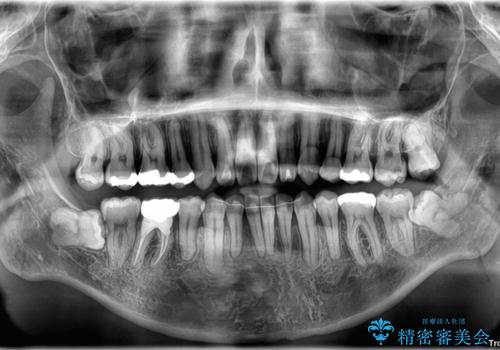

精密検査の結果、上下左右の小臼歯4本を抜歯し、そのスペースに前歯を後方へ移動させる矯正治療をご提案しました。

治療期間は約2年。

少しずつ前歯を後ろに下げていくことで、横顔のラインが整い、口元の“出っ張り感”が解消。